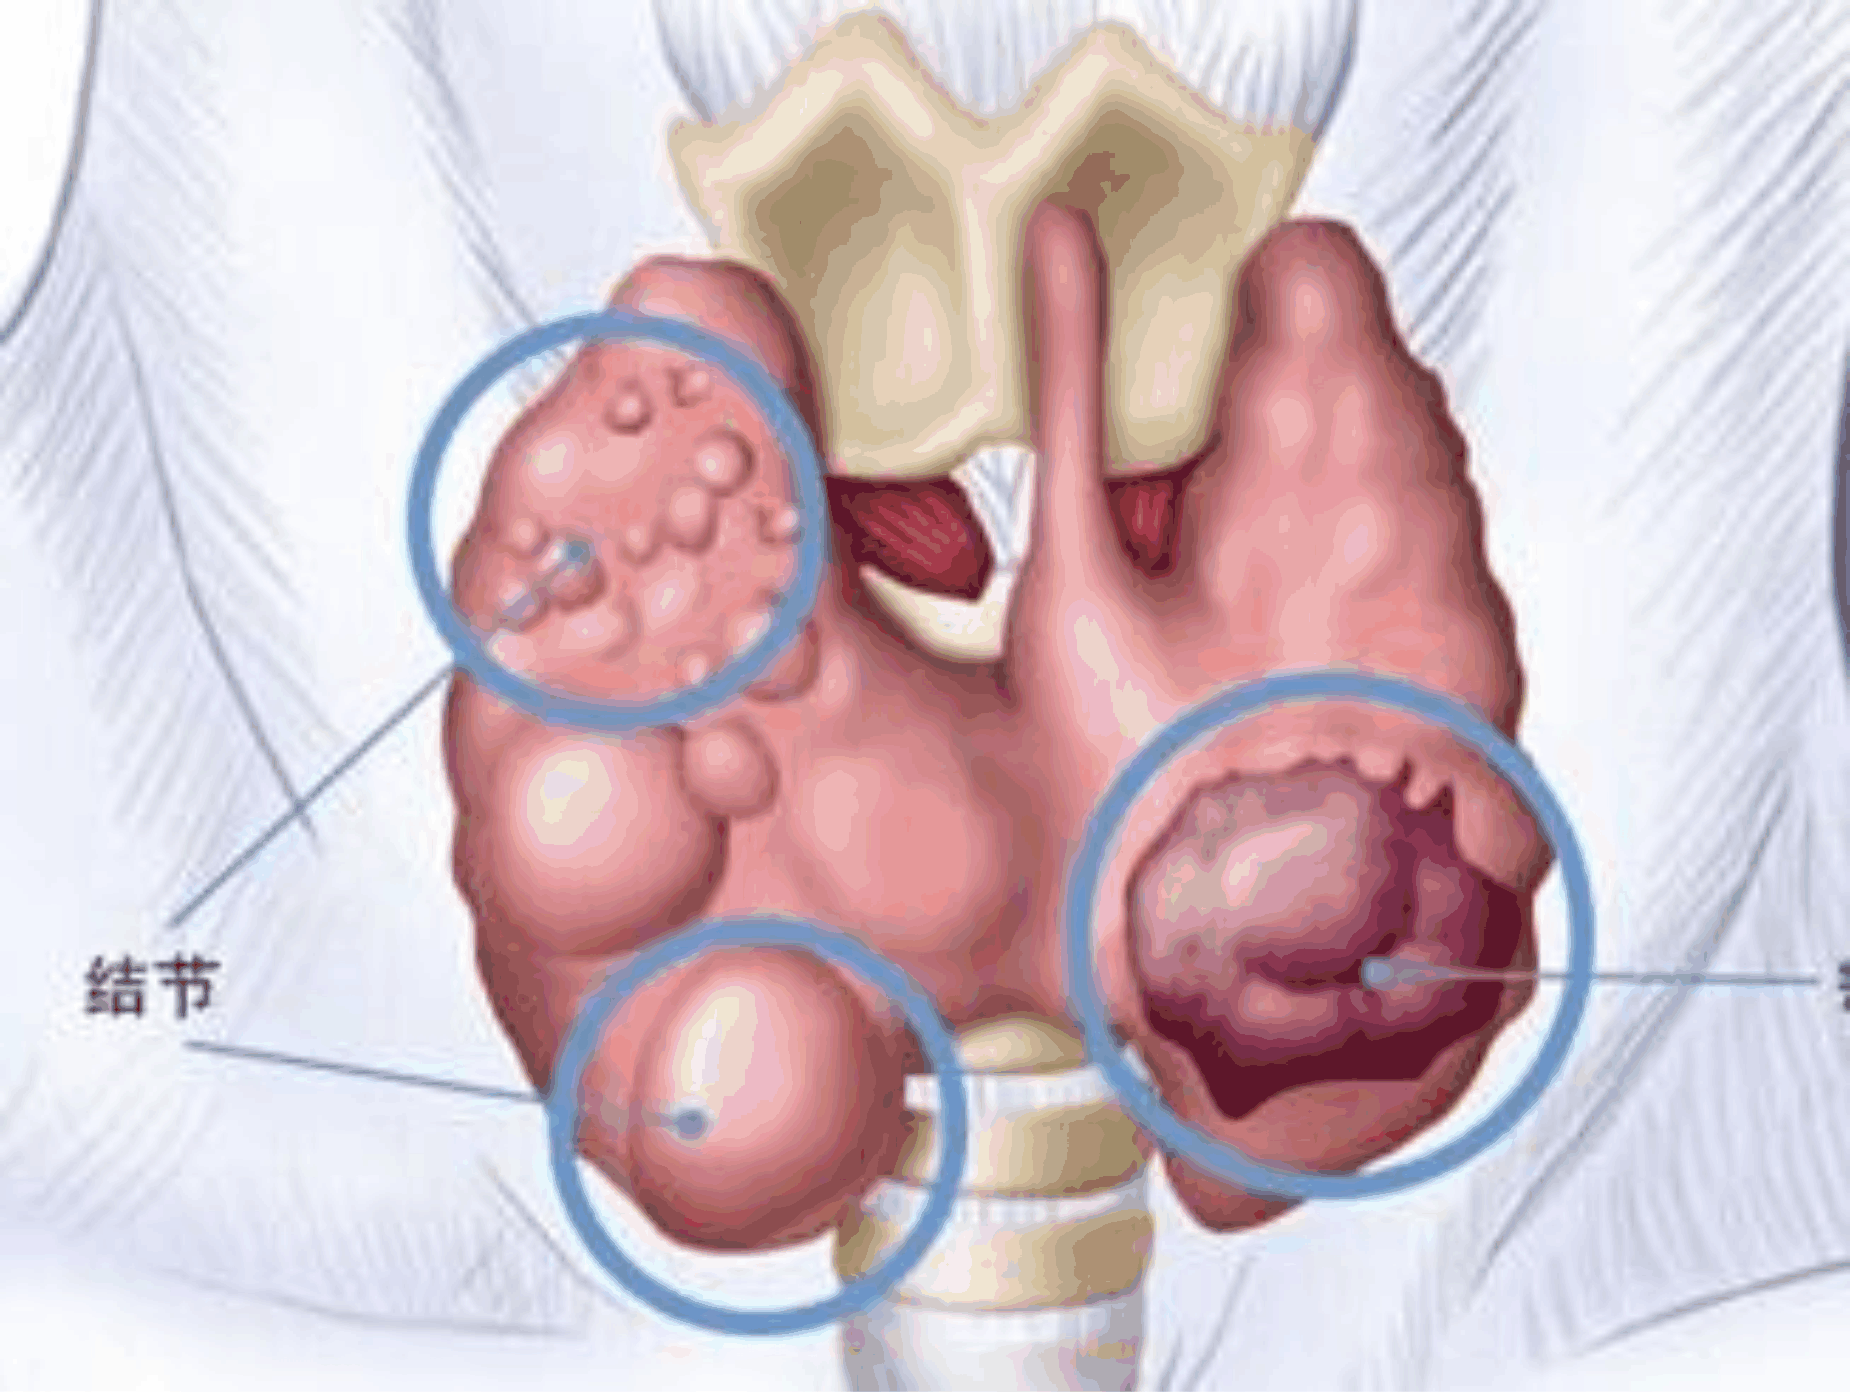

面對身上多出來的“甲狀腺結節(jié)、肺結節(jié)”,需要切掉嗎?

臨床上,常見的有甲狀腺結節(jié)、乳腺結節(jié)、肺結節(jié)等等。長了結節(jié),會癌變嗎?

甲狀腺結節(jié)

甲狀腺結節(jié)是什么?

甲狀腺結節(jié)是內分泌系統(tǒng)常見病及多發(fā)病,是指多種原因導致的甲狀腺內出現(xiàn)的組織結構異常團塊。引起甲狀腺結節(jié)的臨床常見疾病有甲狀腺炎、甲狀腺囊腫、甲狀腺腺瘤、及甲狀腺癌等。

那么,什么樣的甲狀腺結節(jié)惡性的風險大呢?

如果甲狀腺B超檢查報告中,出現(xiàn)低回聲或極低回聲、實性結節(jié)、邊界不清、形態(tài)不規(guī)則、中央血管增多、內見多發(fā)增強小光點(砂礫樣鈣化)等文字時,應該引起警覺,盡快到醫(yī)院就診。

還可以從以下幾個方面來初步判斷甲狀腺結節(jié)惡性的風險:

1.看數(shù)量:單個甲狀腺結節(jié)癌的發(fā)病率要高于多個結節(jié),特別是兒童及青少年單結節(jié)惡性的可能性較大, 男性較女性癌變的機會增加。

2.看大?。?/strong>甲狀腺結節(jié)的大小與它是否會癌變沒有必然聯(lián)系。生長迅速的結節(jié)通常提示惡性可能性大,但急驟增大伴疼痛的甲狀腺腫多為急性甲狀腺炎或腺瘤內出血。

3.看質地:質地光滑、較軟的甲狀腺結節(jié)大多為良性,質地堅硬、邊緣模糊、形態(tài)不規(guī)則、惡性概率大。

4.看活動度:可活動甲狀腺結節(jié)大多為良性,活動度差、固定的結節(jié)考慮甲狀腺癌。